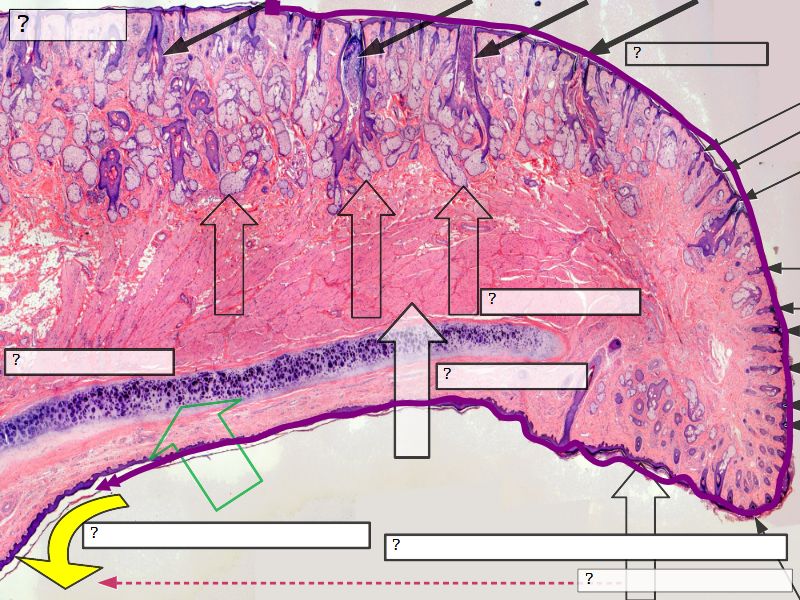

Fill in all the missing labels, and assess as you move through the slides. Answers on the down slide. It is important to do this using pen and paper, and not just glance through the images.